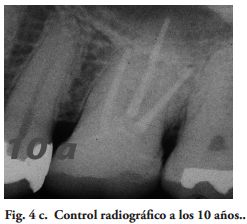

Los exámenes clínicos fueron realizados con un espejo y un explorador agudo. Un control radiográfico fue hecho en cada DPET. La evaluación de las variables relacionada a las restauraciones, fue ciega entre los autores. El Coeficiente Kappa de Cohen (14), en la calidad de las restauraciones y del examen radiográfico, varió de 0.78 a 1 [excelente de acuerdo a la guía de Fleiss (15). En los casos de no concordancia en la calificación, se registró el valor más bajo.

Al momento del examen, 10 (90.9%) EC estaban en función en 10 pacientes. Un molar 26, restaurado con EC, se perdió por enfermedad periodontal después de 12 años y 9 meses en función. Ninguna restauración se desprendió, no hubo recidiva de caries y al examen radiográfico no se observaron lesiones patológicas en los 10 DPET en función (Figs. 1a,1d; 2c; 3c,3d; 4c).